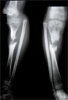

Intra

Op

Ilizarov frame with corticotomy applied